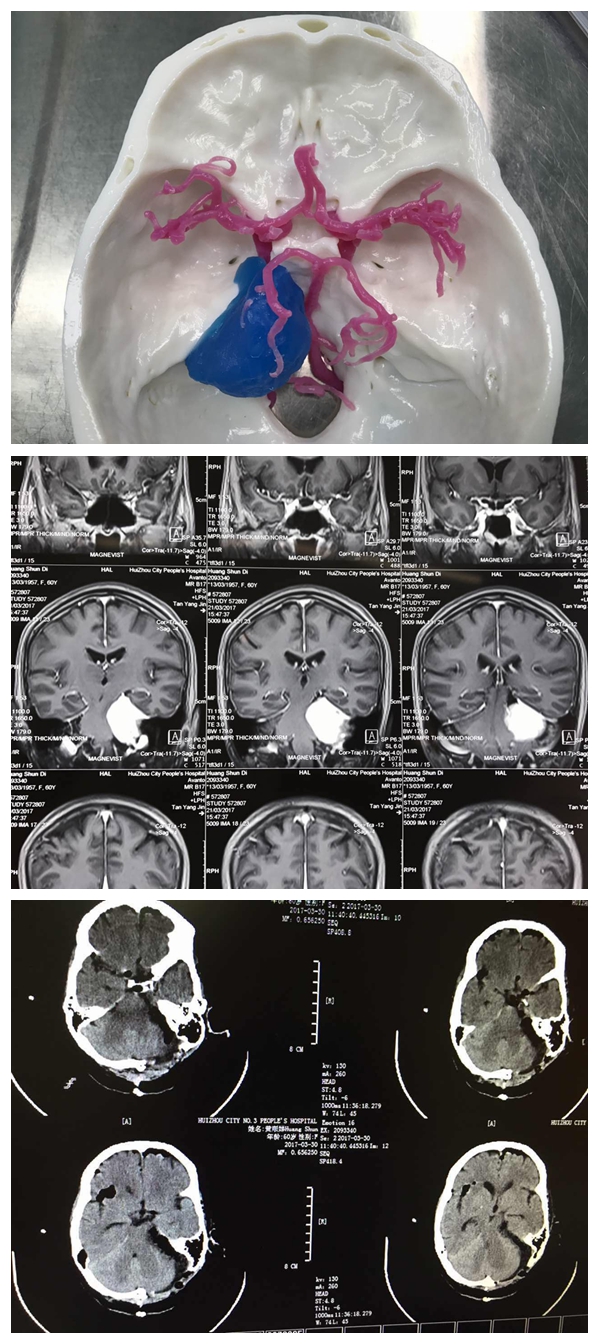

第二例3D模型

第二例為蝶骨嵴內(nèi)側(cè)及海綿竇旁腫瘤切除術(shù),腫瘤包裹了顱內(nèi)重要結(jié)構(gòu)(頸內(nèi)動(dòng)脈及其分支,視神經(jīng)),由于位置深,與重要結(jié)構(gòu)相鄰,腫瘤血供極其豐富,手術(shù)難度大。然而經(jīng)過(guò)3D模型下精準(zhǔn)的定位,以及術(shù)前充分的準(zhǔn)備及討論,手術(shù)順利完成,患者恢復(fù)良好,近期將出院。

第三例3D模型、術(shù)前術(shù)后CT

第三例腦腫瘤位于巖斜區(qū),跨中后顱底,靠近中線,緊鄰腦干全程,上起自天幕,跨天幕裂孔與中腦相鄰;中間經(jīng)過(guò)巖斜區(qū),過(guò)內(nèi)聽道及中線區(qū),與腦橋腹側(cè)緊鄰;向下達(dá)頸靜脈孔及枕大孔外側(cè),與心跳及呼吸中樞延髓相鄰。涉及到腦干及重要顱神經(jīng),包括動(dòng)眼、滑車、外展、三叉、面、前庭蝸、舌咽、迷走、副及舌下神經(jīng)全部被腫瘤影響,血管有大腦后動(dòng)脈、小腦上動(dòng)脈、小腦前下及后下動(dòng)脈相鄰,手術(shù)極其復(fù)雜,難度極大?;颊咝g(shù)前有明顯的面部疼痛及感覺運(yùn)動(dòng)障礙,徹夜難眠、痛苦不堪。對(duì)于該病例,李雪松主任高度重視,做了充分的評(píng)估和準(zhǔn)備,術(shù)中使用神經(jīng)電生理全程監(jiān)護(hù),顯微鏡下配合使用CUSA,雕刻式切除,操作都在毫米空間內(nèi)完成,微創(chuàng)且無(wú)損傷,實(shí)乃精品佳作,患者術(shù)后癥狀完全緩解。

據(jù)李雪松主任介紹,這一例可以說(shuō)是世界級(jí)的高難復(fù)雜顱底腫瘤顯微外科手術(shù),腫瘤全切且腦功能及神經(jīng)血管完美保留,神經(jīng)功能保留完好,臨床癥狀完全緩解,實(shí)屬不易。